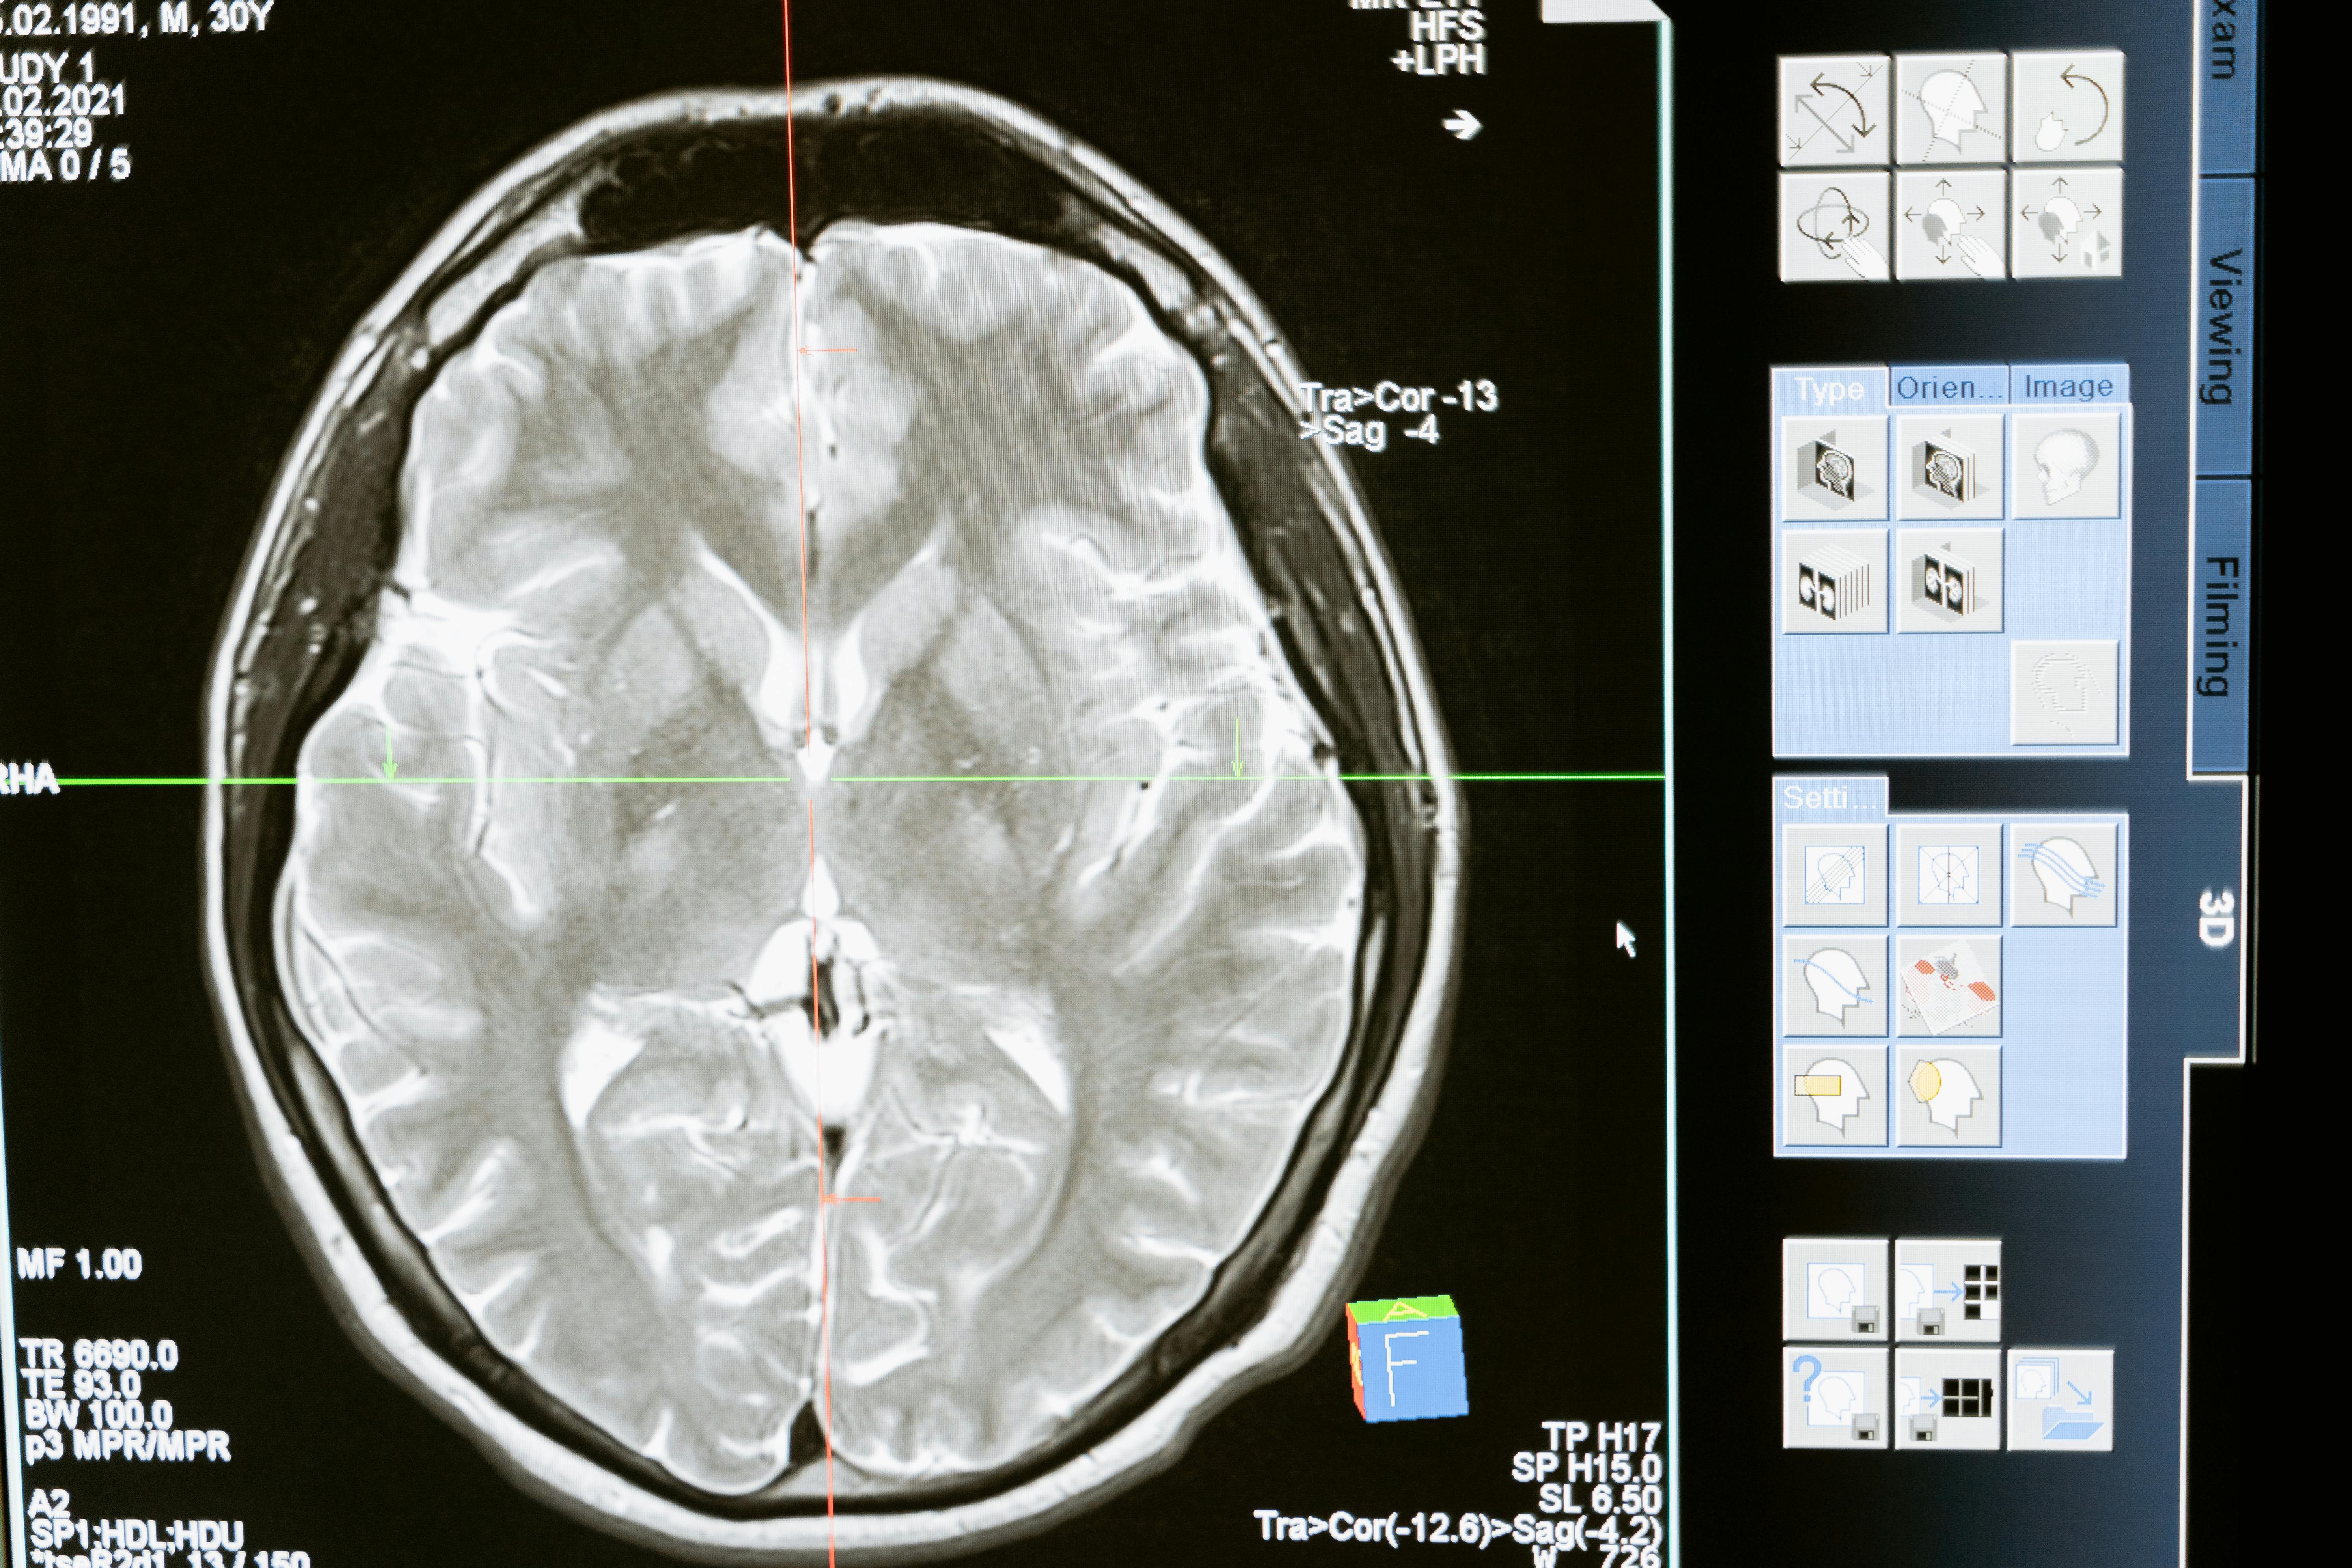

Radiología Digital